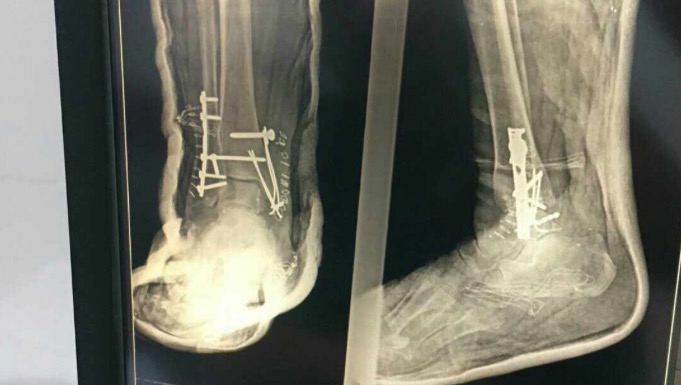

My mother suffered a severe leg injury, requiring a platinum implant. She battles diabetes and desperately needs treatment beyond the confines of the Gaza Strip, along with proper healthcare and the right medications.